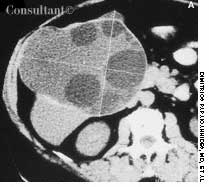

In the web space of his left hand, a 50-year-old barber had a painful cystlike lesion. The lesion had recurred intermittently, despite oral antibiotic treatment and warm compresses. The patient's father, also a barber, had a similar, more severe condition, which eventually required surgical intervention.